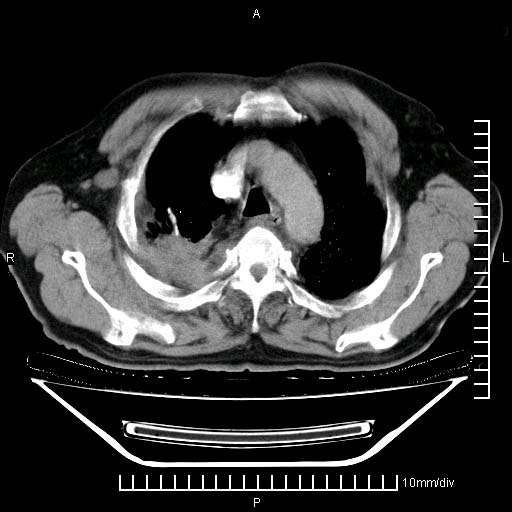

既往肺结核,近10几天,咳嗽,咳痰,右侧胸痛,疼痛较明显,右上肺斑块考虑结核灶胸膜粘连,增强,可惜动脉期没有定好,未见强化,可延迟4分后又见较明显强化,中心见低密度影,如果说结核是边缘强化,可这个灶强化的面积挺大的,让人很挠头。

动脉期